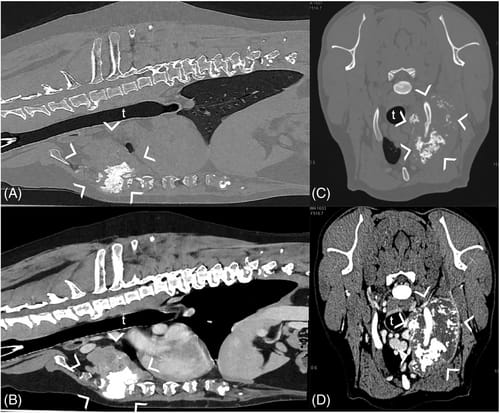

Examples of neoplasia arising from the sternum (A, B) and from the rib (C,D). A,B, Sagittal reconstruction of the thorax of a dog with sternal OSA (between arrowheads), bone window (A) and post-contrast soft tissue window (B) showing a large, heterogeneous mass, with mineralized and soft tissue components, occupying the cranial aspect of the thoracic cavity. C,D, Transverse plane in bone window (C) and post-contrast soft tissue window (D) of the cranial thorax of a dog with OSA of the second left rib (between arrowheads), characterized by mixed attenuation, with large mineralized portions, and invasion of the thoracic cavity. t = trachea. Helical modality, 120 kVp, 200 mAs, image matrix 512 × 512, 0.5 mm slice thickness.